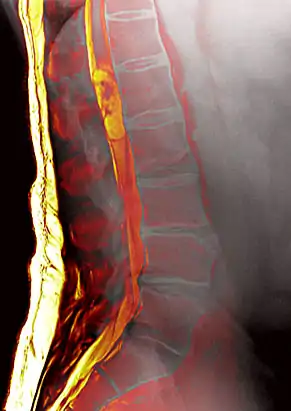

Image fusion of plain radiograph and T2W MR image of lumbar spine in a patient with an ependymoma centered at L1 and a limbus vertebra at L4. These images were registered manually using the OsiriX Zoom and Move tools.